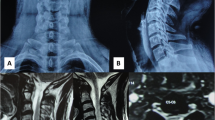

A very rare case of intradural extra-arachnoid schwannoma involving the upper cervical spine is described. The tumour most likely originated from the extra-subarachnoid angle region, with its unusual pattern of expansion within the spinal canal resulting from such characteristics of the upper cervical region as a relatively wide spinal canal, an extensive ventral subarachnoid space, and membranous ventromedian and lateral anchoring structures which influenced the direction of tumour enlargement.